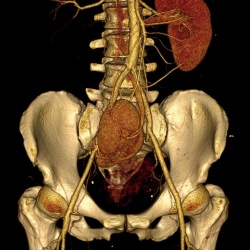

поступает женщина. Гематурия. По УЗИ - образование почки.Делаю КТ с фазным контрастированием.Вроде всё ясно, пишу ПКР правой почки. Однозначно нефрэктомия. Смотрим распространенность процесса

Пациентка 64 лет, обратилась с жалобами на болезненность в мезогастральной области, по данному УЗИ абдоминальное: объемное образование правой почки.